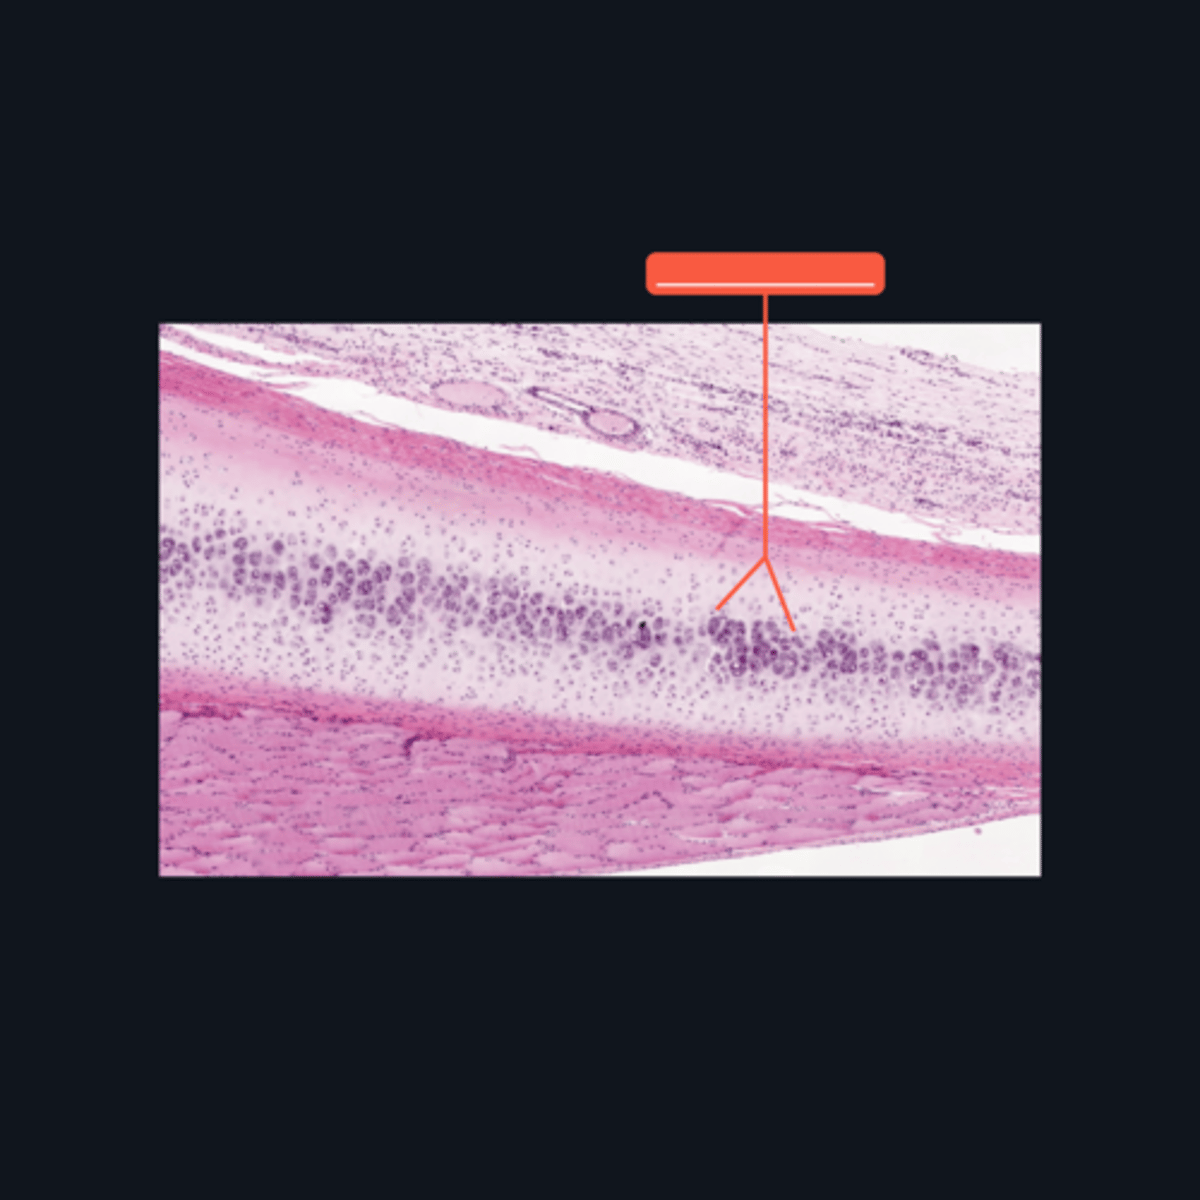

Epiphyseal Plate

Identify the pointed structure

End of the increase in length of bone

What signifies the closure of the pointed structure?

A - Zone of Resting Cartilage Cells

B - Zone of Proliferation

C - Zone of Maturation

D - Zone of Calcification

E - Zone of Ossification

Identify the pointed structures

B - Zone of Proliferation

Which pointed structure is the zone where instestitial growth occurs and what zone is it?

E - Zone of Ossification

Which pointed structure and what zone where many of the cavities left by cartilage cells merge to form marrow cavities?

C - Zone of Maturation

Which pointed structure and what zone do not divide anymore?

A - Zone of Resting Cartilage Cells

Which pointed structure and what zone anchors the epiphyseal plate to the epiphysis?

D - Zone of Calcification

Which pointed structure and what zone where the cartilage matrix is calcified